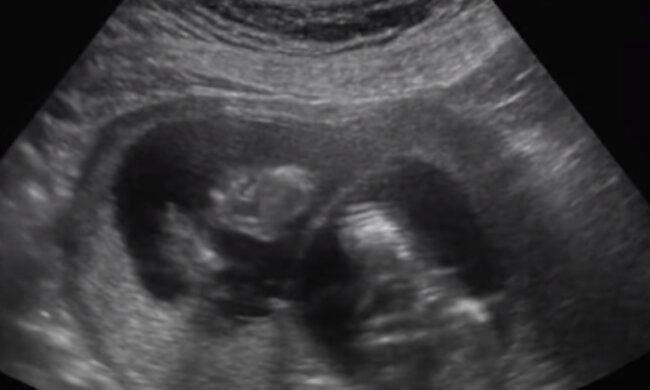

Z życie wzięte. Marta miała 45 lat, postanowiła, że chce mieć dziecko. Gdy powiedziała o swoim planie rodzinie, wszyscy byli przeciw

Miała stabilną pracę i mieszkała z mężem w domu, który kupili kilka lat wcześniej.